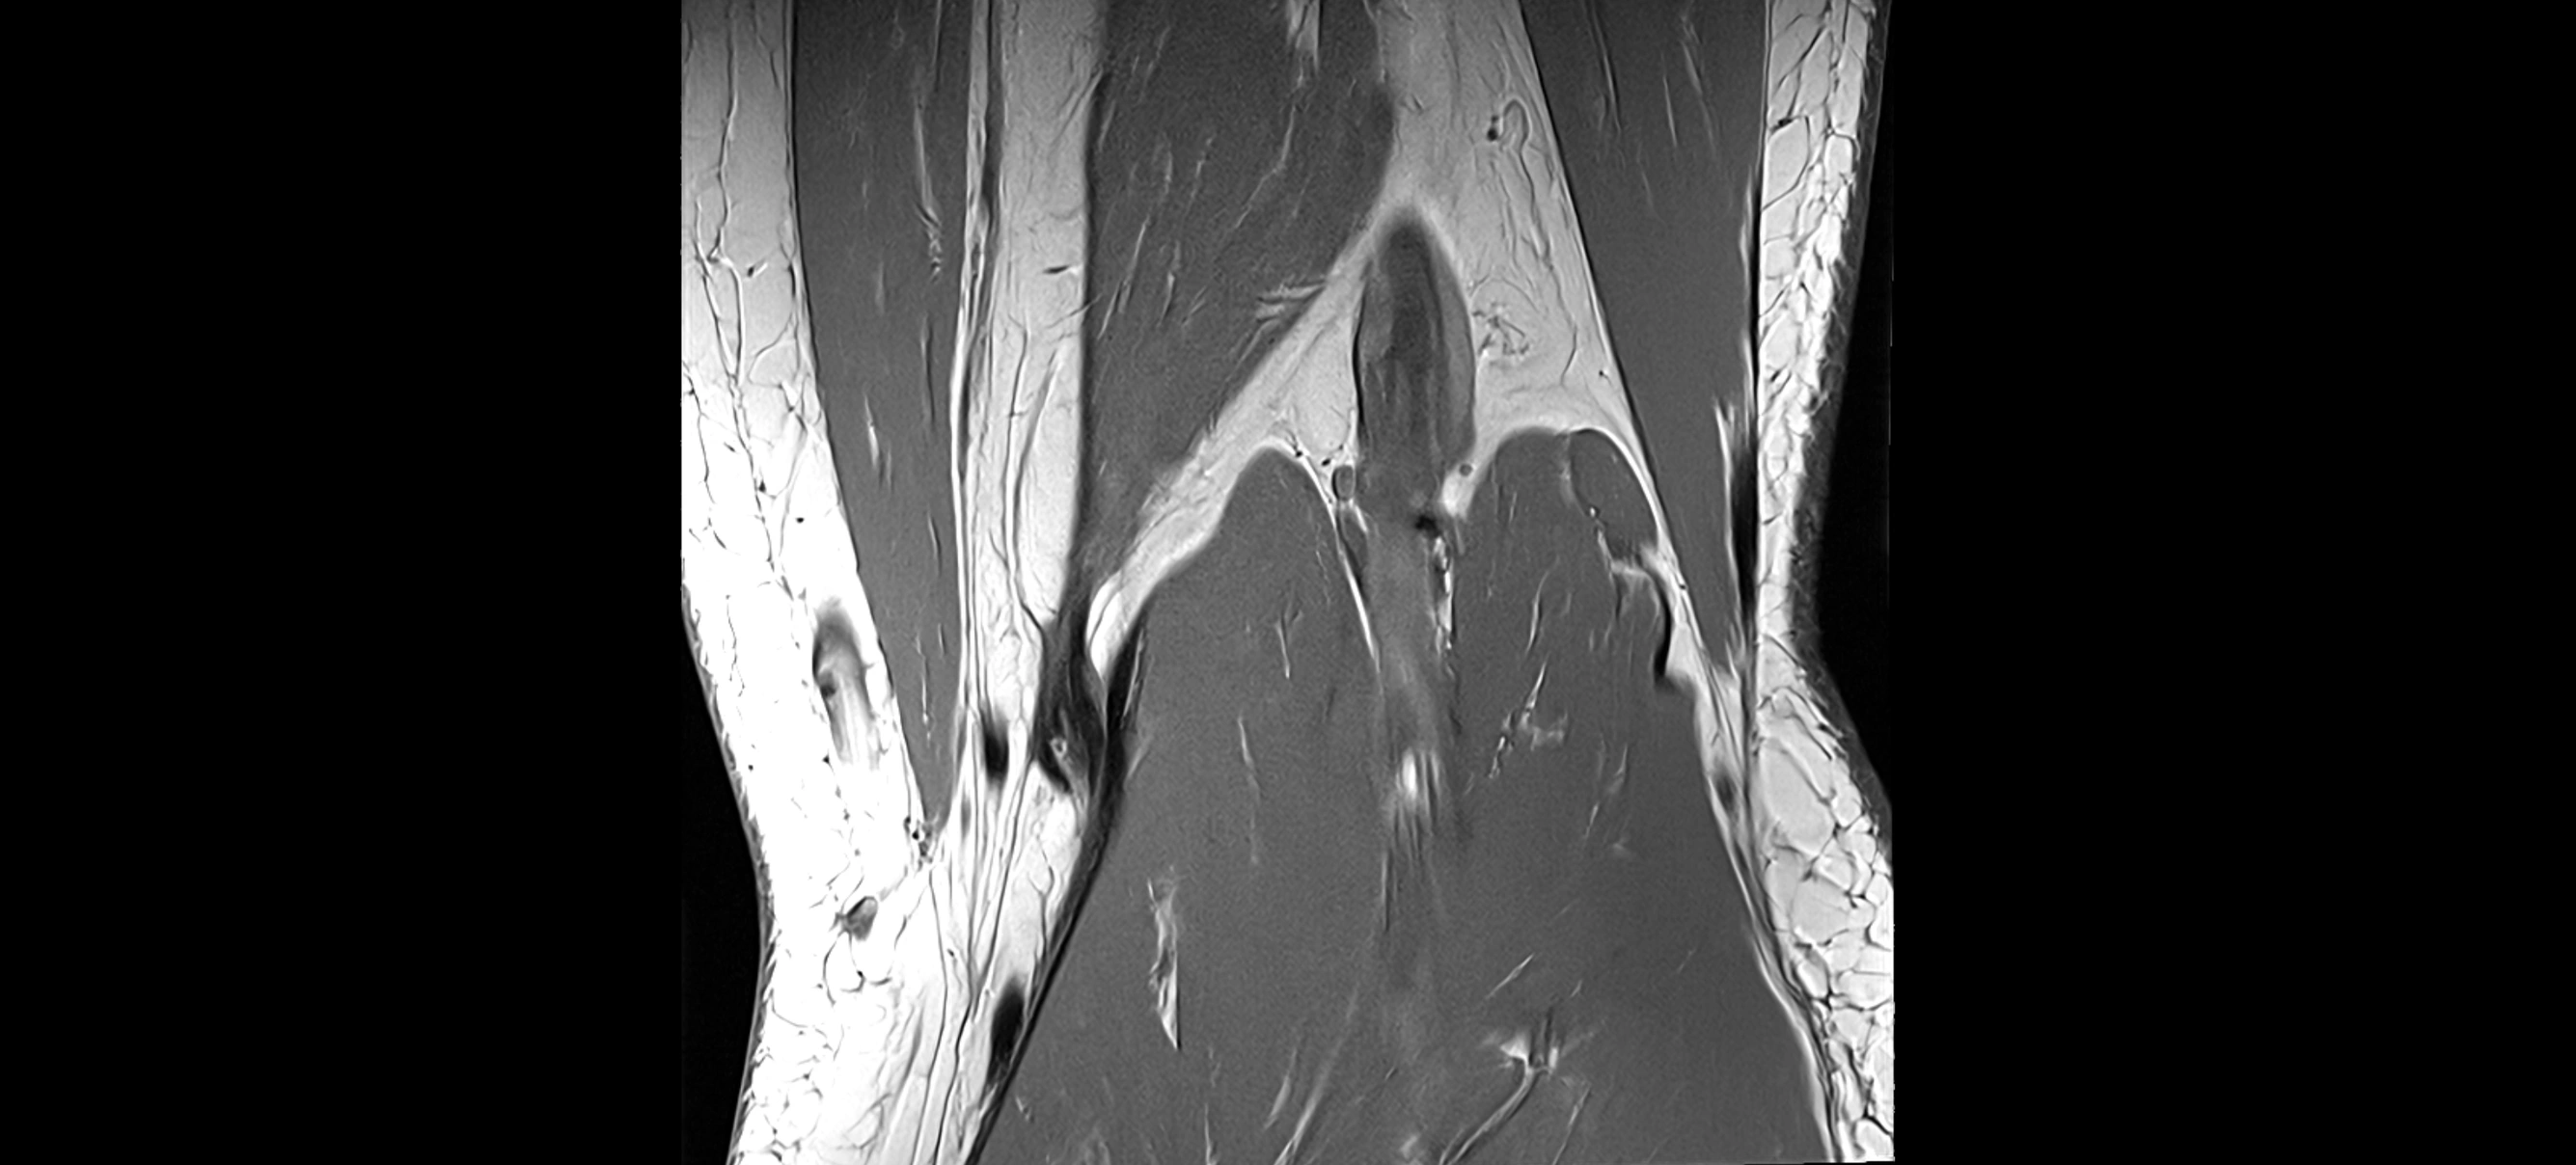

MRI images

image

MRI Appearance

T1-weighted images:

• Normal ACL appears as a low-signal band-like structure crossing the intercondylar notch

• Surrounded by intermediate signal synovial fluid and fat planes

T2-weighted images:

• Normal ACL remains low signal

• Partial or complete tears appear as discontinuity, increased signal, or fiber laxity